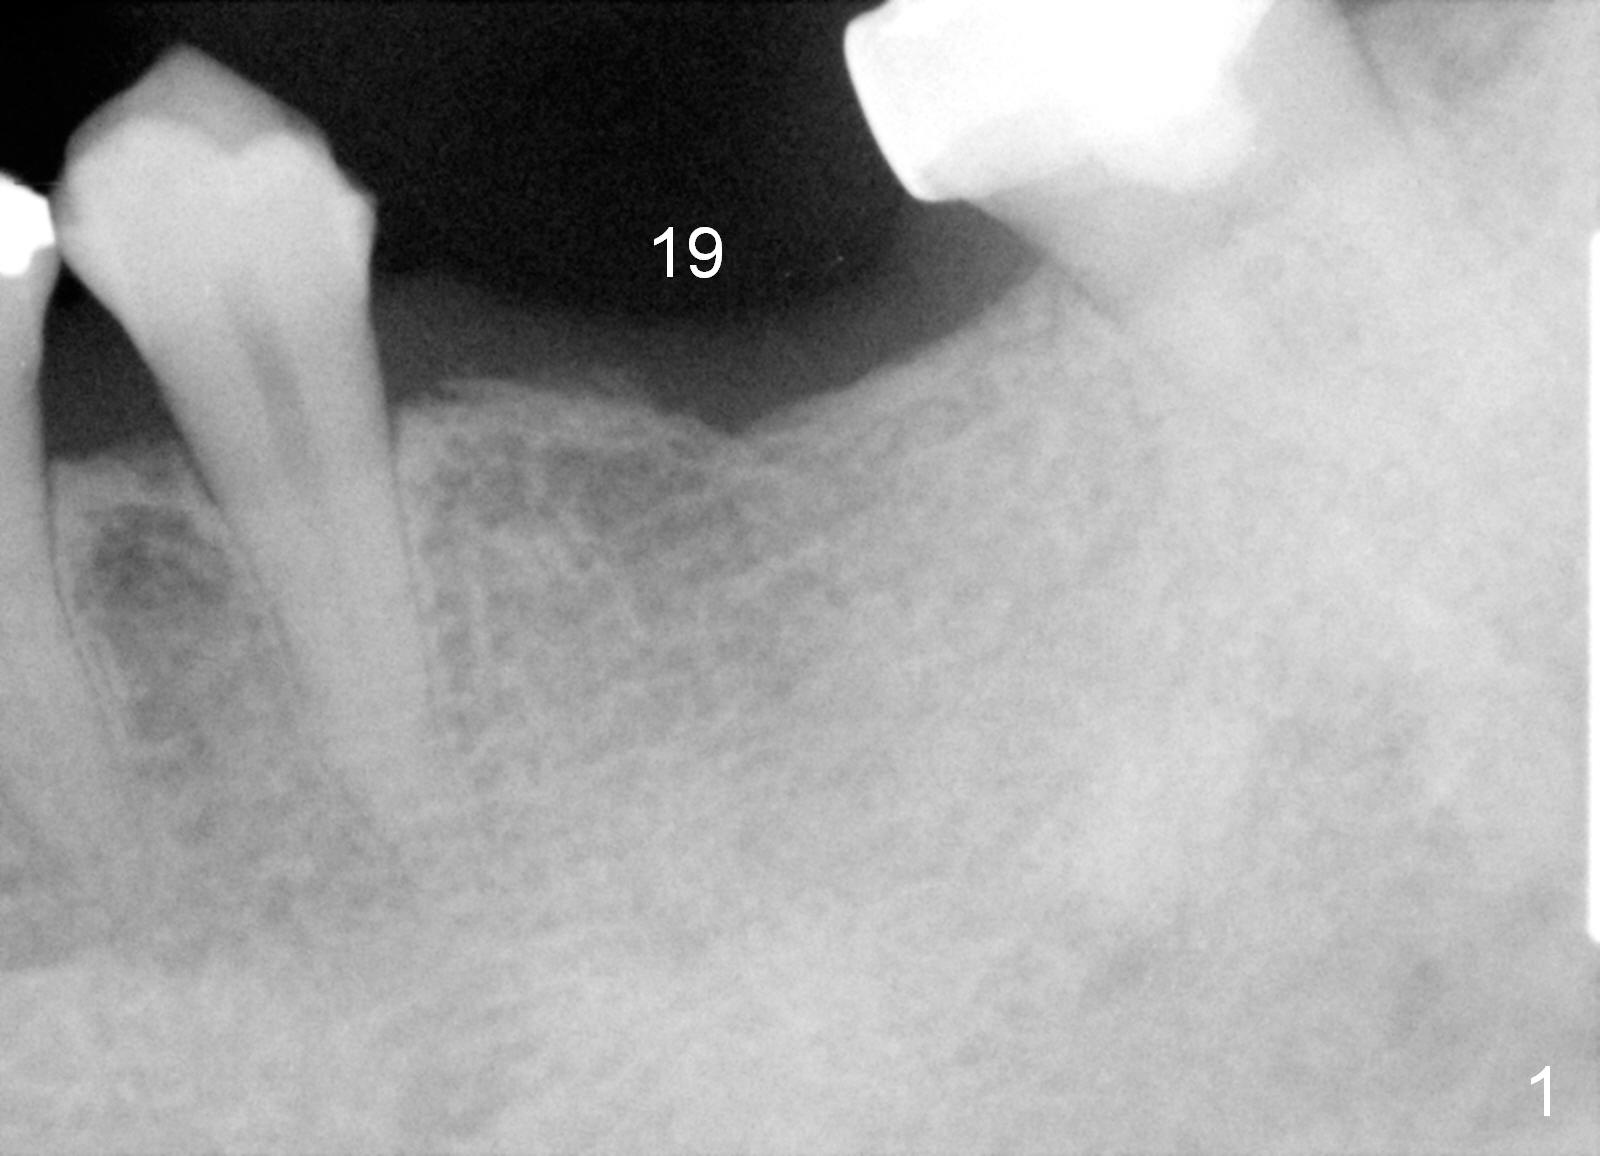

A 45-year-old man has lost the tooth #19 for about a decade (Fig.1).  In spite of this, the ridge is not particularly narrow.  The bone height is good for 14 mm bone-level implant (Fig.2).  After incision, initial osteotomy depth is 12 mm.  Insert a short parallel pin for occlusal check and a depth-marked parallel pin for X-ray.  When the depth is adjusted, use drills with stoppers to finish osteotomy.  If bone density is low, the drill is one size smaller than the expected implant.